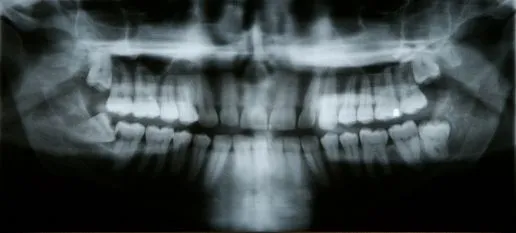

A tooth becomes impacted when there is not enough room to accommodate the space in the dental arch and growth becomes impossible.  After surgery to remove an impacted tooth, mild discomfort and some swelling is expected. This is part of the process and should not alarm you. You may use cold compresses to alleviate the swelling. In addition, your doctor will prescribe pain medication, which should be taken as directed. Patients are also advised to favor the extraction area and modify their diet for a few days to allow for healing.